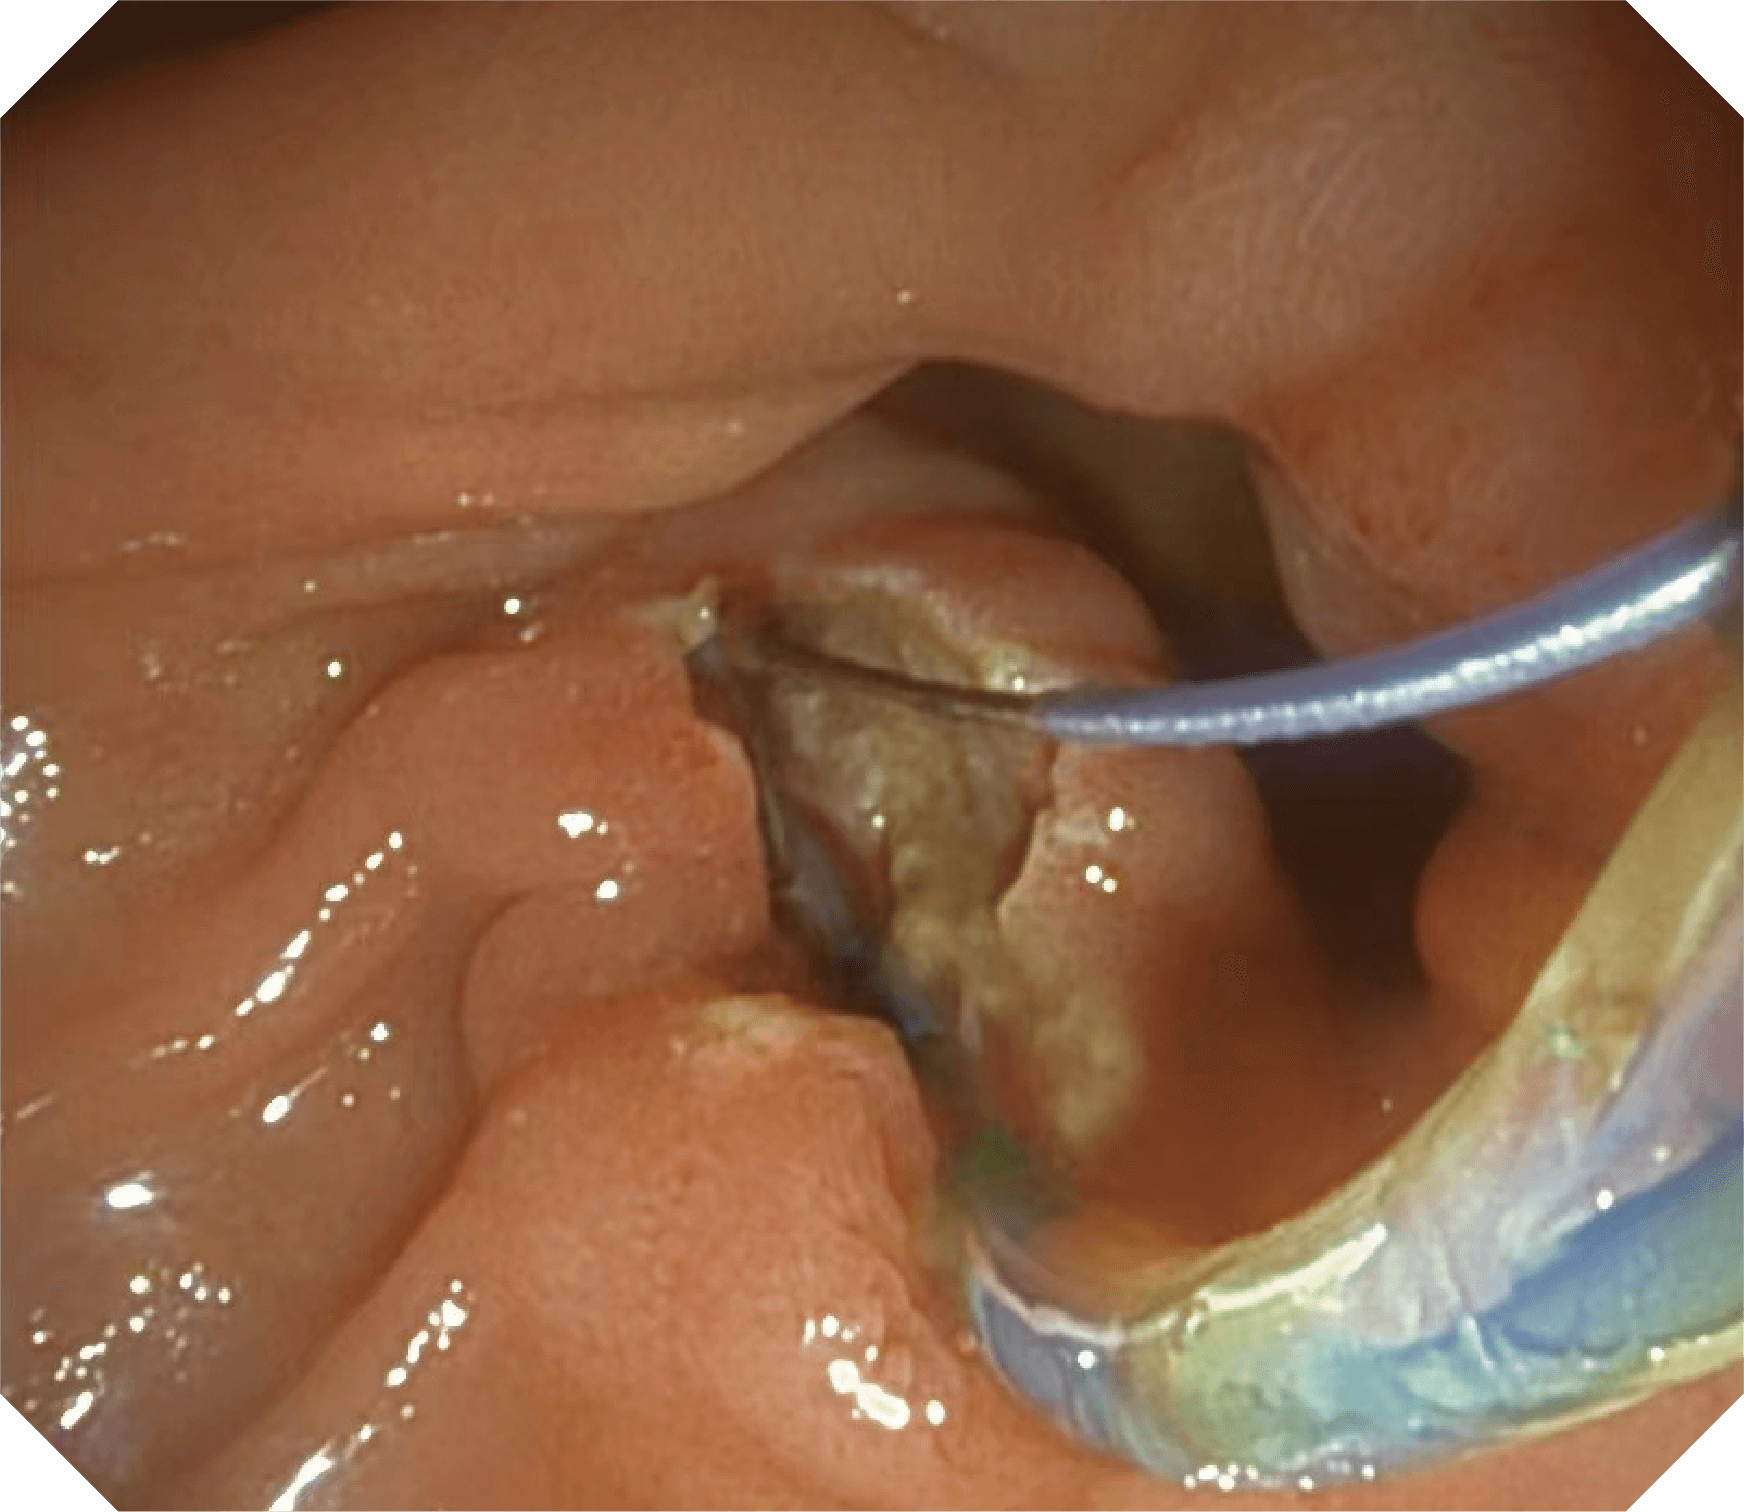

导丝机械锁紧功能

V槽设计提升导丝控制

当切开刀伸出视野外时,导向面引导其回归视野